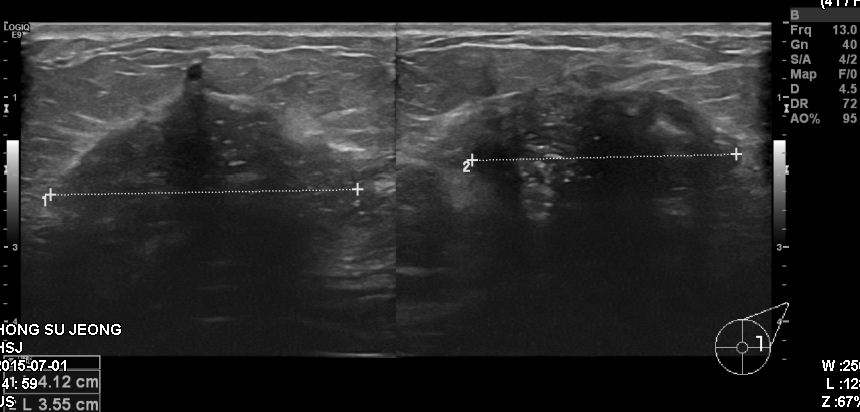

상기환자 건강검진상 이상 소견으로 내원하신 40대 여성분으로 본원 조직검사 시행 후

좌측 침윤성 유관암 진단 되었습니다.